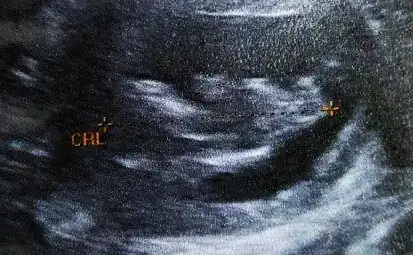

6. Hafta , 7. Hafta (ikisi de vaginal) ve 11+5 haftalık usg

yorumlarınızı heyecanla bekliyorum .